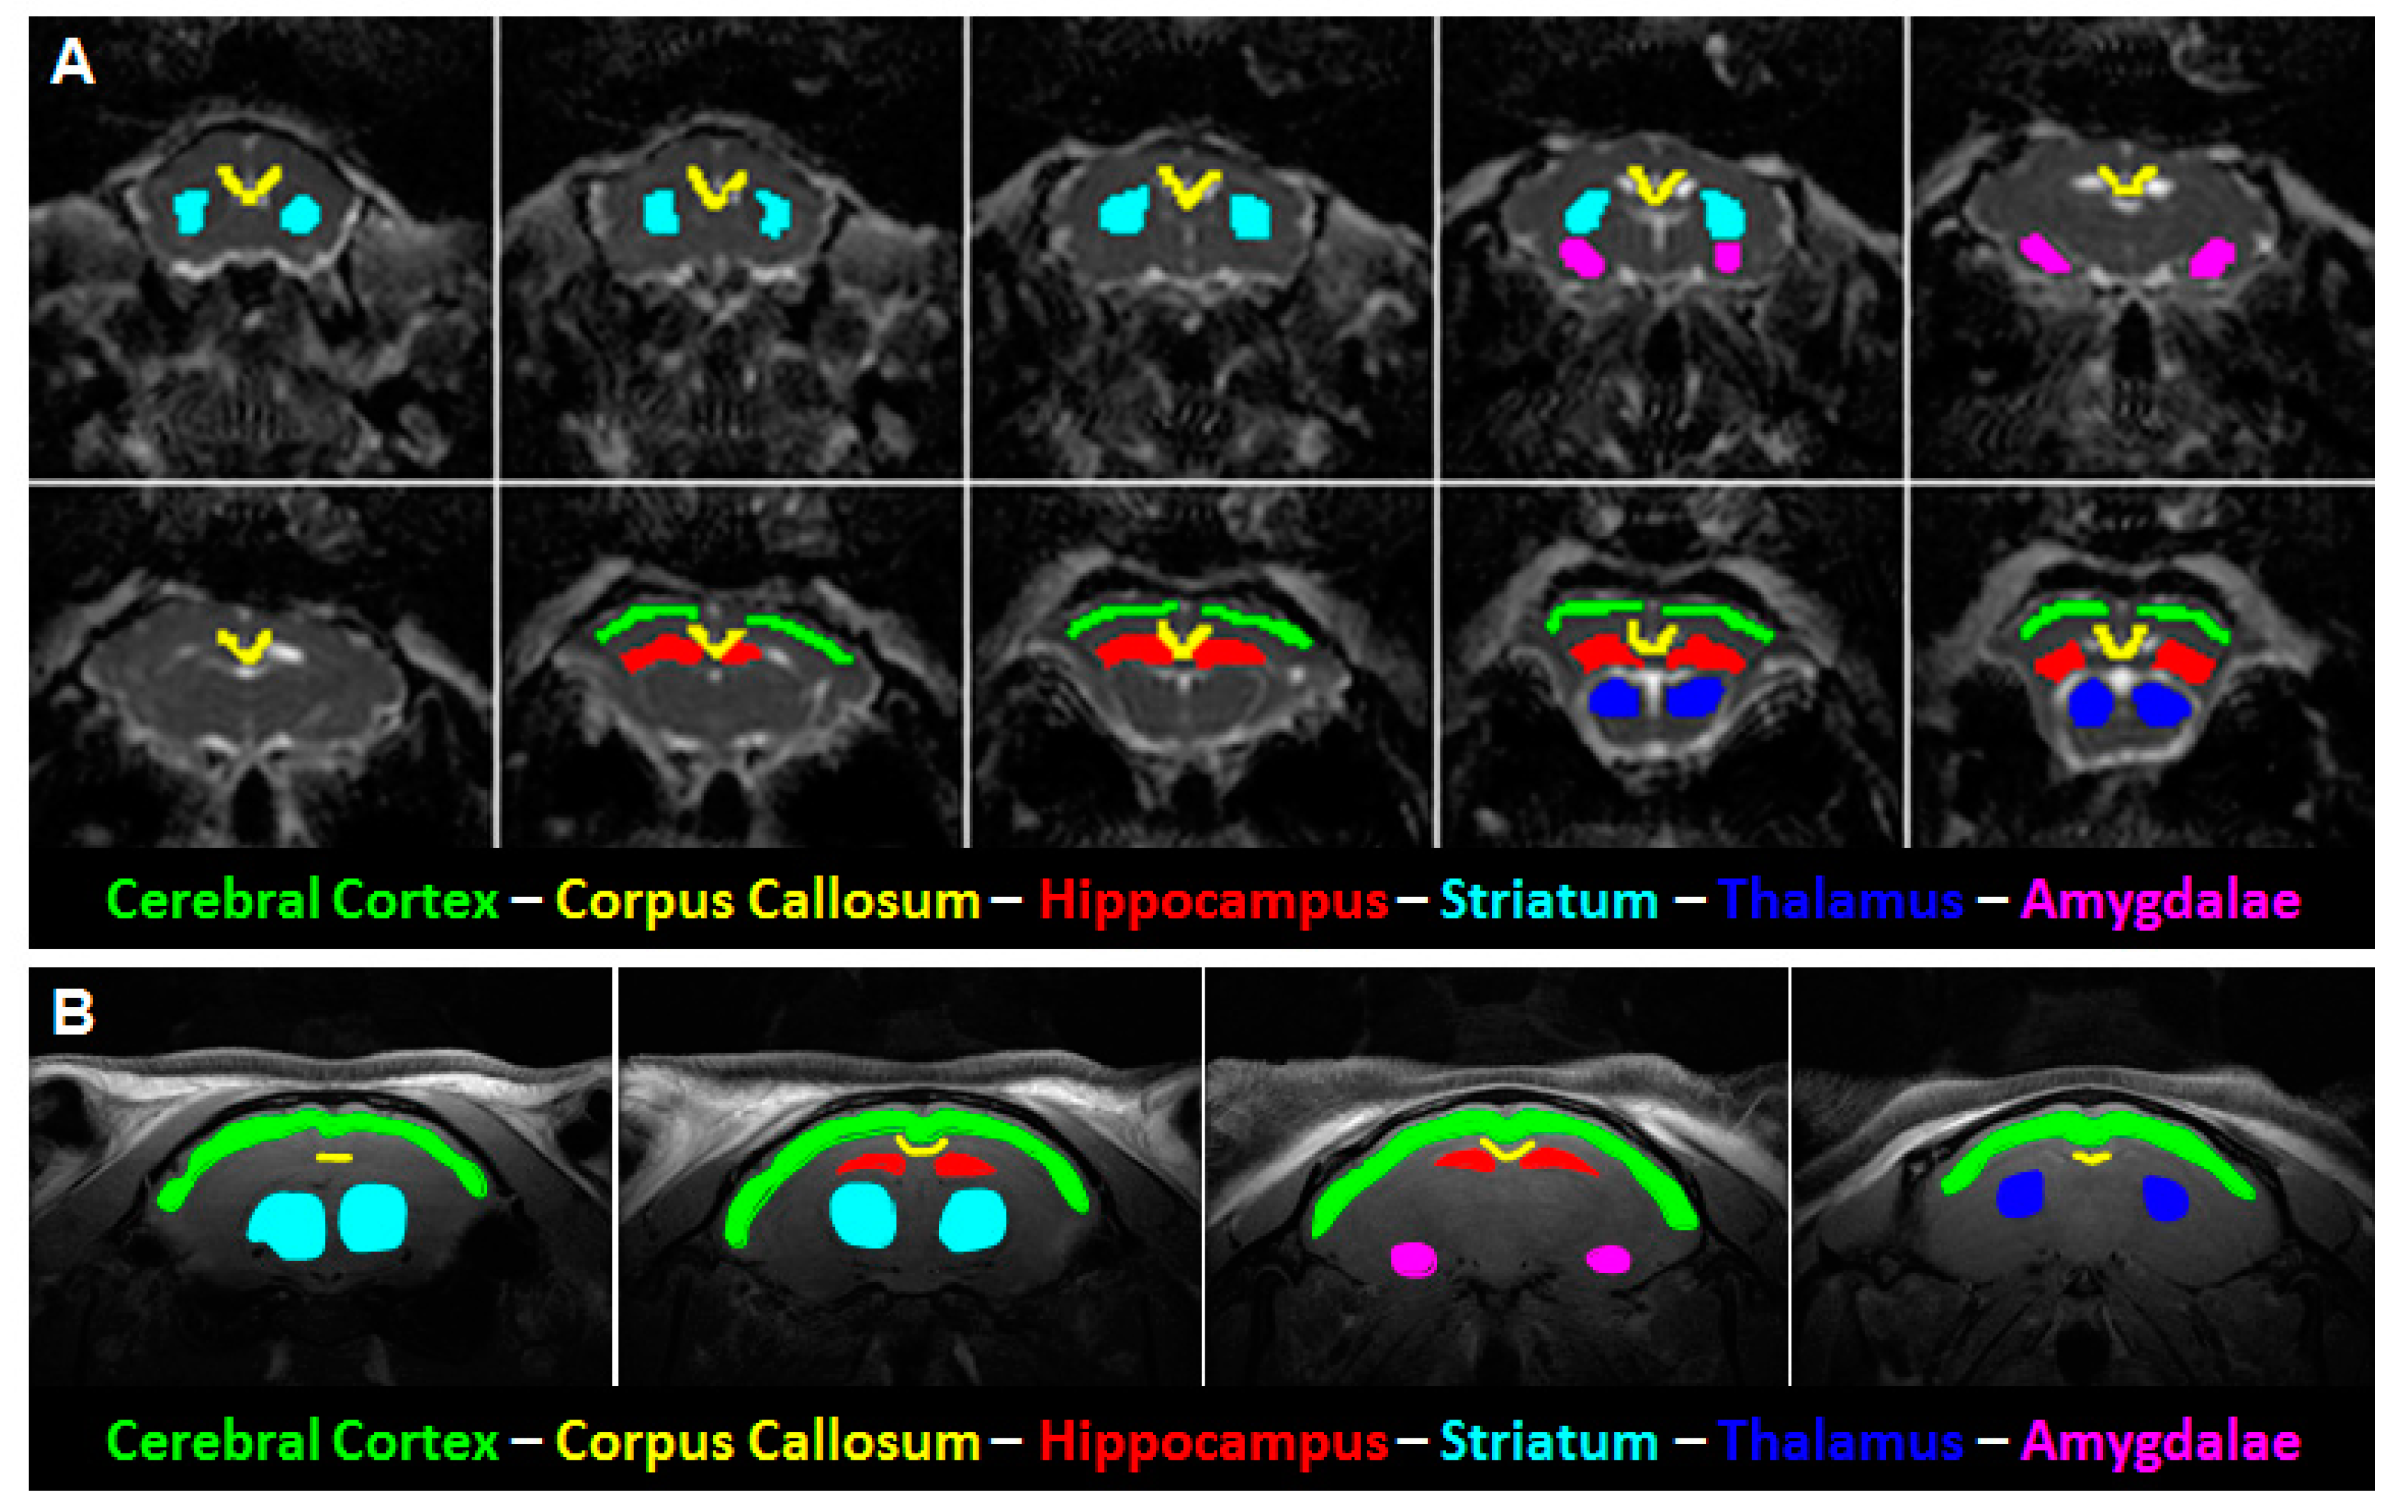

2.3. Data Processing

3.3. Age Dependence of Regional FA

3.4. Age Dependence of Regional Diffusivity Measures

3.5. Age Dependence of Regional Kurtosis Measures

3.6. Age Dependence of Regional T2 Relaxation Time